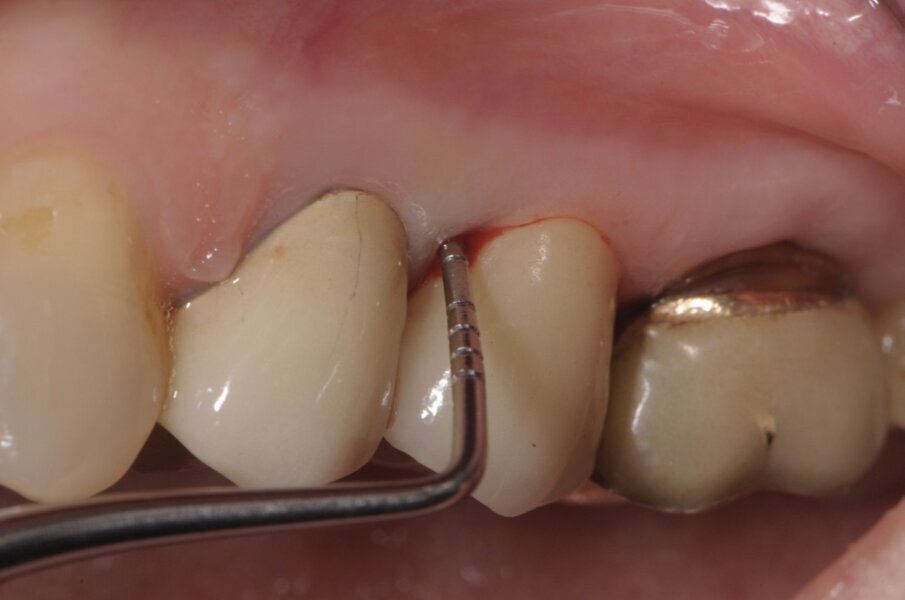

La terapia endodontica estesa agli elementi adiacenti ha consentito di eseguire un provvisorio che ha permesso alla paziente di non subire il disagio estetico e funzionale del mancato carico dell’impianto. Dopo due mesi si è provveduto a rilevare le impronte per la riabilitazione finale. Abbiamo utilizzato un sistema digitale (Trios-Trishape) che seguendo la procedura di lettura rileva le varie impronte dal provvisorio, al tragitto transmucoso, in tal caso è necessario provvedere a posizionare i fili retrattori che siamo soliti utilizzare nella lettura del finish line e solo al momento della lettura andiamo a rimuovere il 2° filo e a svitare la vite di guarigione o il moncone provvisorio così da non determinare il collasso dei tessuti del tragitto transmucoso implantare (Fig. 6). Dopo l’impronta dei tessuti e dei monconi degli elementi naturali si procede a segnalare gli elementi da protesizzare (Fig. 7) e successivamente si posiziona il transfer dell’impianto che nel sistema digitale è rappresentato dallo scan body o corpo di scansione (Fig. 8).

Fig. 6 - Posizionamento dei fili retrattori secondo la tecnica del doppio filo, appena prima dell’impronta si procede alla rimozione del II° filo e della vite di guarigione implantare.